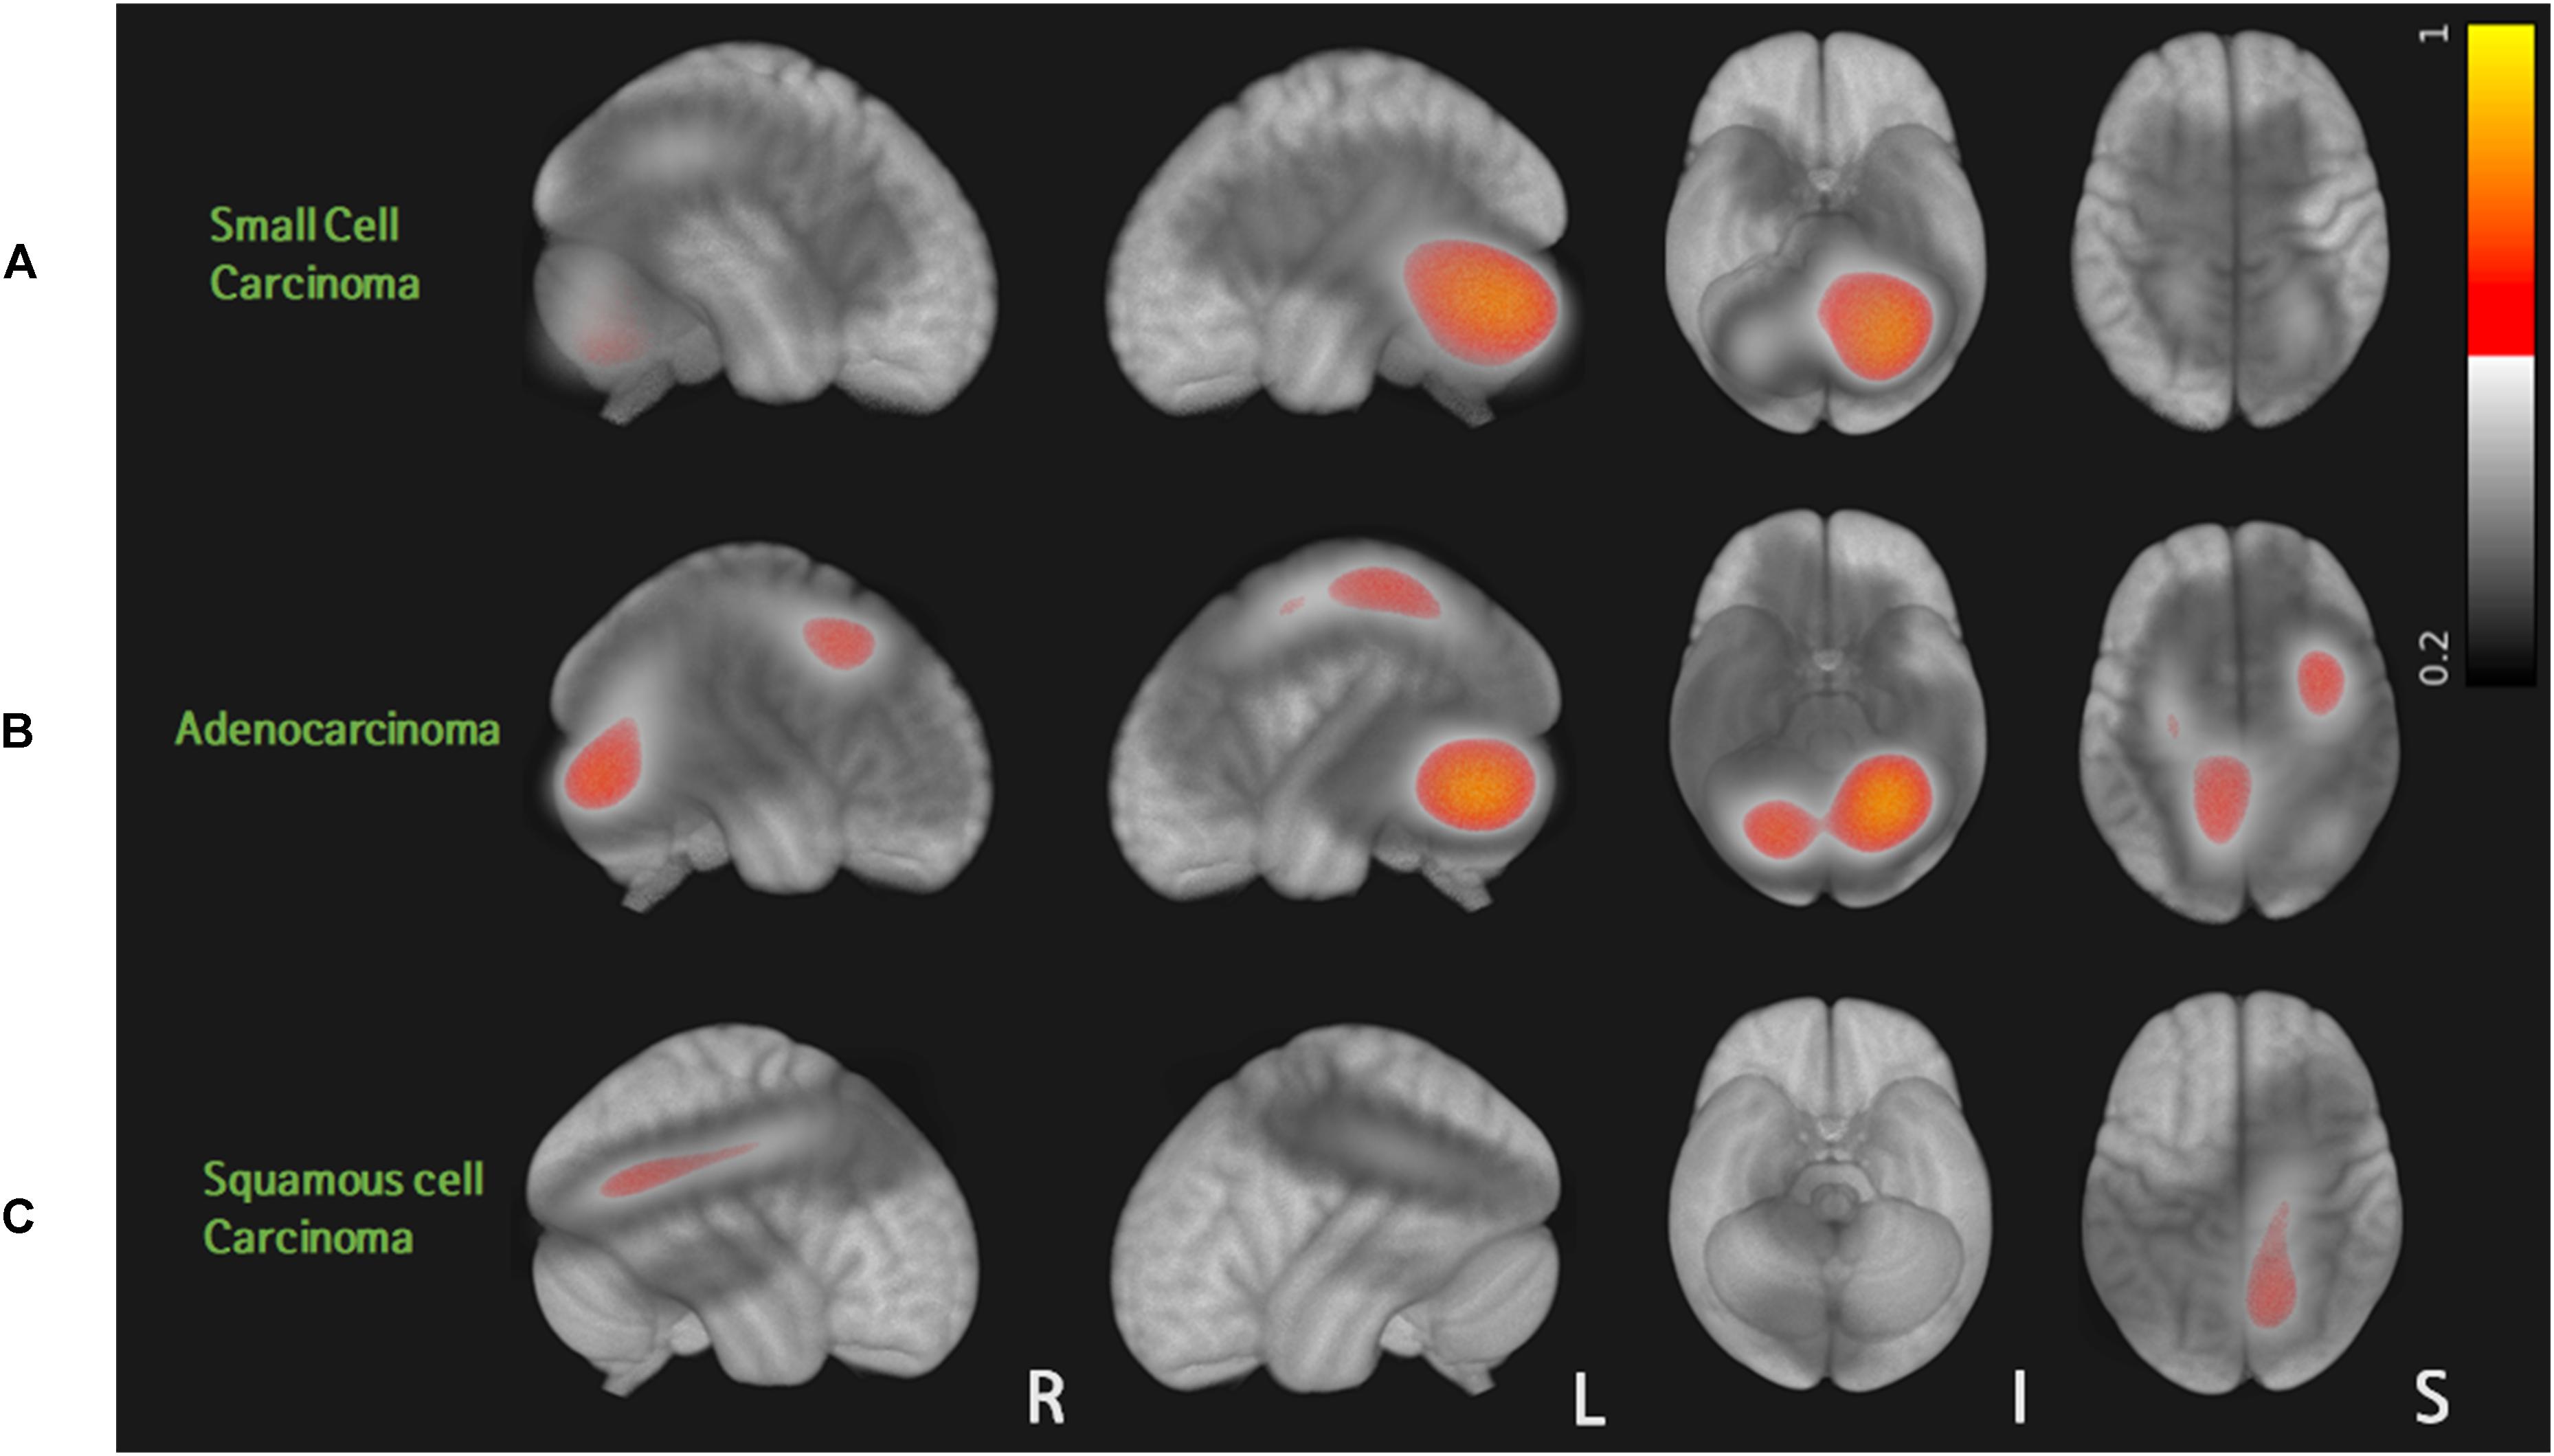

A total of 80 patients with 562 metastases were included in this study: 13 cases of small cell carcinoma with 107 BMs, 58 cases of adenocarcinoma with 432 BMs, and 9 cases of squamous cell carcinoma with 23 BMs. Table 1 summarizes patient characteristics. Sex, smoking history, RPA results, and BM volume were significantly different among the three groups (p < 0.05). Probabilistic density functions showed different spatial distribution of BMs according to histologic subtypes of primary lung cancer (Figure 2). For small cell cancer, BMs were frequently found in the cerebellum. For adenocarcinoma, BMs were clustered in the cerebellum, distal MCA, and ACA territories. For squamous cell carcinoma, BMs were frequently observed in the right parietal lobe.

Figure 2. Probabilistic density function of brain metastases from three different histologic types of lung cancer: for small cell carcinoma, BMs were frequently found in the cerebellum (A). For adenocarcinoma, BMs were clustered in the cerebellum, distal MCA, and ACA territories (B). For squamous cell carcinoma, BMs were frequently observed in the right parietal lobe (C).